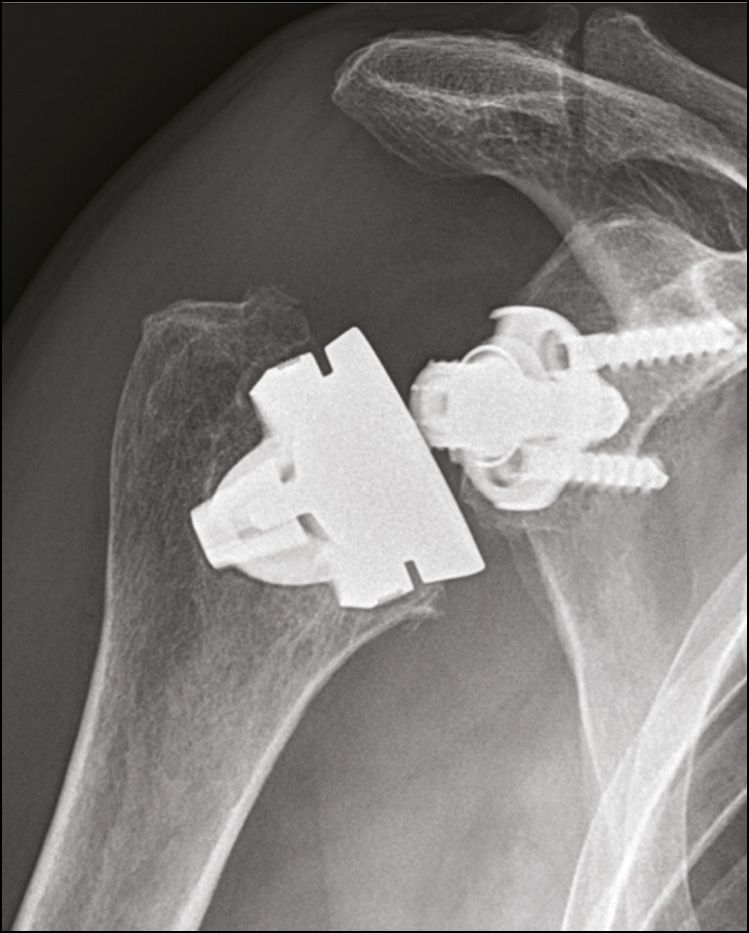

Surgeons and manufacturers are therefore more sceptical or reluctant towards the idea of using stemless RTSA, although the first stemless RTSA, the T.E.S.S. (Zimmer Biomet)[1] Philippe Teissier et al., « The TESS Reverse Shoulder Arthroplasty without a Stem in the Treatment of Cuff-Deficient Shoulder Conditions: Clinical and Radiographic Results », Journal of Shoulder and Elbow Surgery 24, no 1 (janvier 2015): 45-51, https://doi.org/10.1016/j.jse.2014.04.005., was introduced in France in 2006. Since then, the Easytech (FX Solutions, 2013) [2] Nourissat Geoffroy, « Prothèse totale anatomique d’épaule avec Implant Easytech : résultats et trucs techniques », 282, mars 2019, Maitrise Orthopédqiue édition. and SMR Stemless (Lima, 2014) (Fig. 1) have consolidated the interest in this bone-sparing method (both these implants are currently awaiting authorisation for the American market).

For all patients the Lima SMR implant had been used. This implant has a glenosphere (40mm or 44mm diameter) which comprises two-thirds of a non-eccentric polyethylene sphere. The humeral cut is made at 135° using a guide, and the metaphyseal insert (three thicknesses) is at an angle of 7°, which puts the CCD angle of the RTSA at 142°. We make our cuts with 20° retroversion.